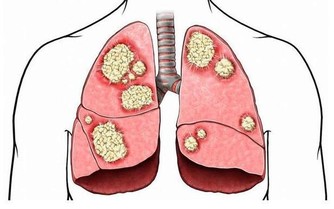

記得剛做住院醫生的時候,那時對卵巢癌患者做化療,

藥物中順鉑已是必備藥,而且現在這個藥還是卵巢癌化療的首選藥。

順鉑這個藥物對改善卵巢癌患者的預後起了很大的作用,

使80年代前的1年成活率不到20%,在使用這個藥後其2年成活率超過80%。

現在這個藥也用於其它惡性腫瘤的化療。

但這個藥有個很大的毒副作用,就是損傷腎臟,像氨基糖甙類抗生素一樣,引起腎小管壞死。

但最近卻一連發現有3位患者,在進行到第4個療程的時候,出現了不同程度的腎功能受損。

當然,我們首先想到的是順鉑對腎臟的損傷,但這幾個病人的腎臟代償能力怎麼就這麼差呢?

帶著這個問題,我在隨訪中對這幾個病人的飲食習慣問了一下,發現她們的確都和我一樣,喜歡吃蘑菇。